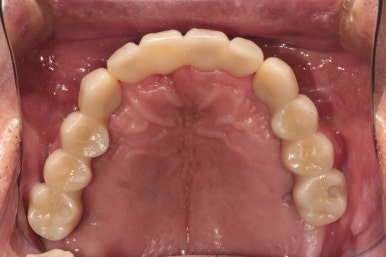

이루 말할 것 없이 깔끔하게 정리된 교합면 사진입니다.

사실 각 어금니마다 1개씩 임플란트가 더 식립되는 것이 28개의 치아를 재건하는데 필수적이나, 남성임에도 불구하고 턱이 아주 크진 않으셨기에 24개의 크라운만으로도 충분히 만족스러운 결과를 얻을 수 있었습니다.!!

다시봐도 지르코니아 크라운의 색상은 너무나 자연스러운 것 같아요... 상당히 완성도 있게 마무리 되었던 케이스였습니다. 개원 초기부터 믿고 잘 따라와주심에 감사드립니다 :)